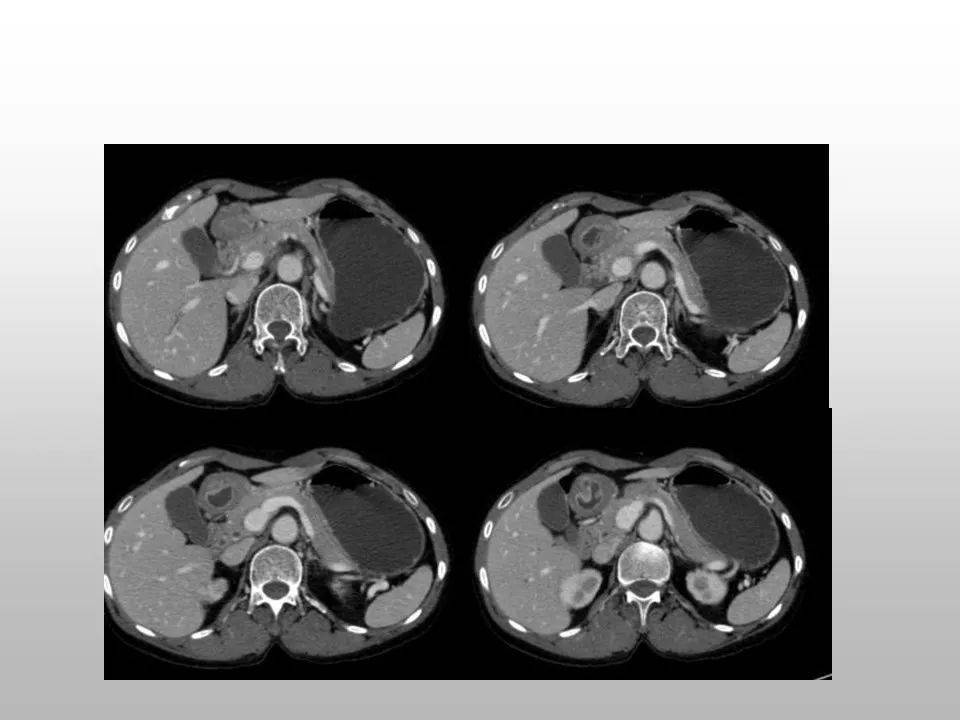

第四步胃癌

经历前三步的逐步展开积累,渐渐就胃癌就来了。作为最罕见的恶性肿瘤之一,胃癌晚期缺少特异性病症与体征,因此常常招致得到最好医治机遇。